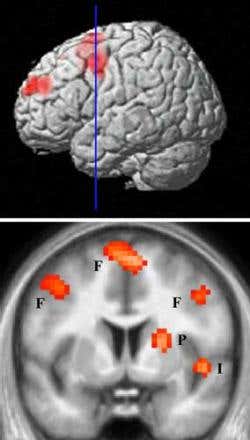

The “hate circuit” of the brain – areas that activate when looking at a hated person – revealed by fMRI scans. F = frontal cortex; P = putamen; I = insular (Credit: UCL)

The results showed two brain regions that our “hate circuit” shares with the “love circuit” – the putamen and the insular cortex or insula.

The putamen is thought to be used to prepare the body for movement – so it’s possible this be active either to provide protection of the loved one, or to prepare for an aggressive or spiteful act from the hated one. The insula is associated with feelings of distress, such as jealousy.

However, there was also an important difference. The areas of the frontal cortex associated with judgement and reasoning are typically less active when viewing a lover compared to someone more neutral, meaning they are less likely to feel critical of their partner.

The hate-filled subjects, though, only showed a reduction in one small part of this area, while the rest was still active.